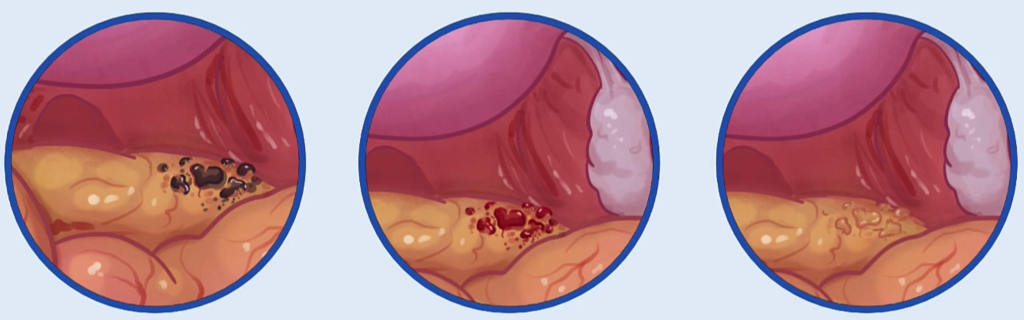

这里有一个临床要点!在腹腔镜下,子宫内膜异位病灶的外观差异很大。有些病灶呈“火药烧灼”状,或呈黑蓝色,也可能呈红色甚至透明。需要记住的是,患者的疼痛程度可能与腹腔镜下所见并不一致。疼痛的程度更多地反映了病灶侵入的深度,而非病灶的数量。